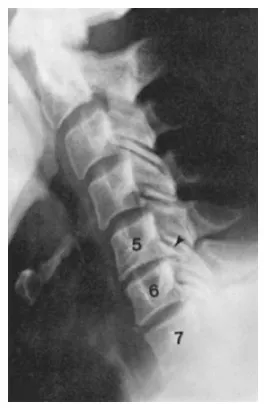

你有沒有發現自己開始脖子僵硬、轉動時卡卡的? 甚至感到頸部、肩膀或手臂疼痛,有時還會麻木或無力? 可能還會感到頭暈、頭痛,嚴重時甚至影響日常生活。這些都是頸椎退化的警訊! 頸椎退化會導致關節和椎間盤磨損,骨刺增生,壓迫神經,產生不適。 本篇內容生硬,但可以詳盡告訴你發生什麼問題。